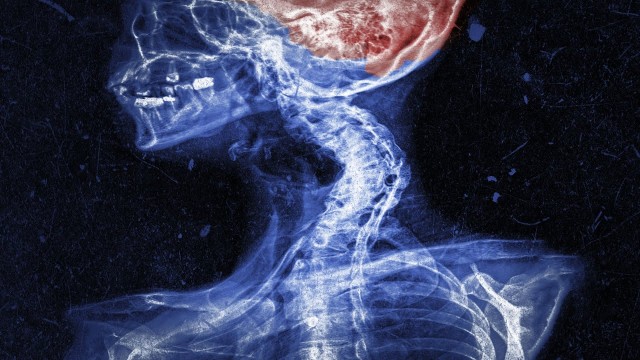

• S2020E02 A Dad Drank 50 Beers Everyday For 6 Weeks. This Is What Happened To His Brain.

Patient JW was someone who presented to an ER in Chicago, early 2013, not Whang.